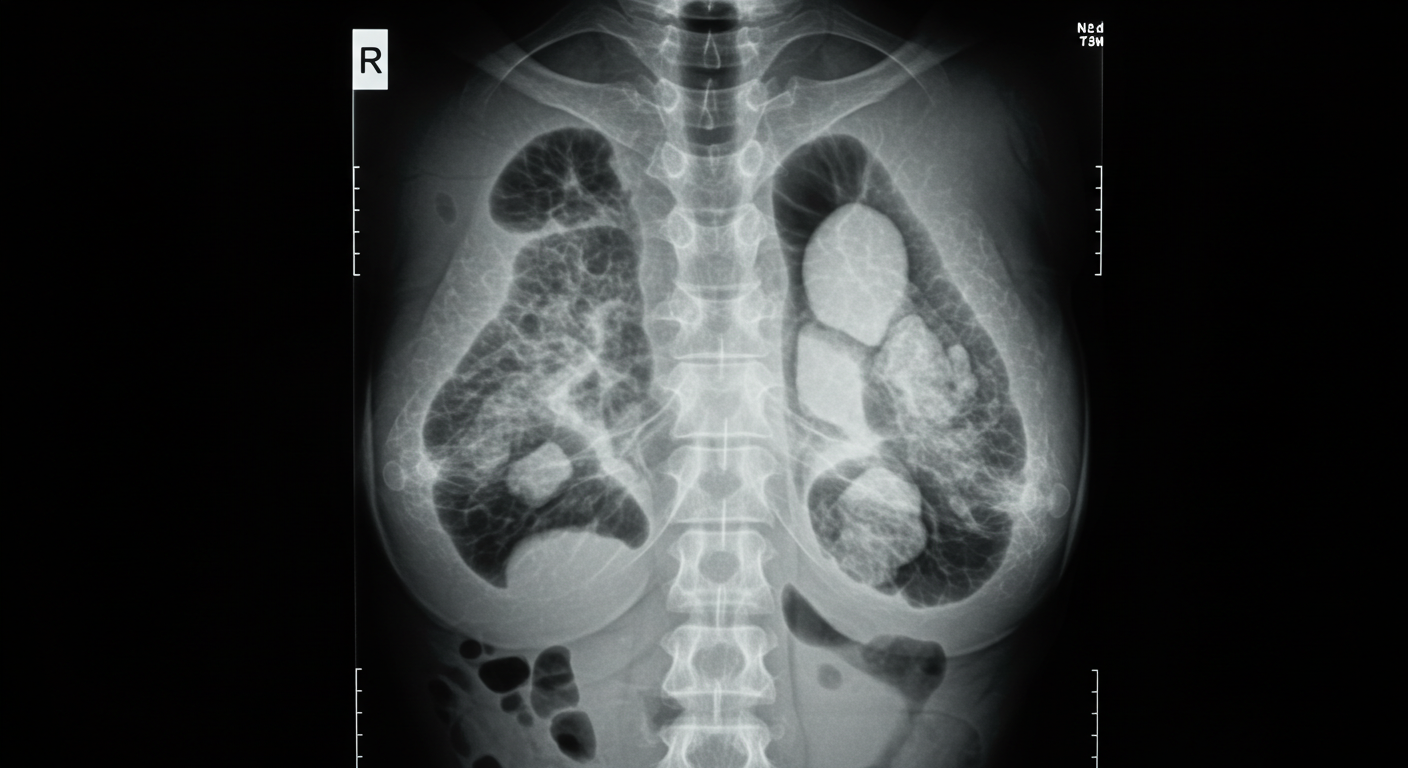

유방 조직 내에 칼슘이 침착된 상태를 말하며,

X-ray에서 하얗게 보입니다.

유방 석회화와 초기 유방암을 나타내는 미세 석회화의 차이

초기 유방암에서도 **미세 석회화(Microcalcification)**가 나타날 수 있어요.

차이점은 모양, 크기, 분포에 있습니다.

구분 양성 석회화 초기 유방암 (미세 석회화)

크기 0.5mm 이상 0.5mm 이하

모양 일정하고 동그렇거나 팝콘 모양 불규칙하고 다양한 모양

분포 여러 군데 산재 한 부위에 군집

진행 암 가능성 거의 없음 조직 변화 진행 가능 → 검사 필요

☞ 즉, 석회화가 있다고 해서 바로 암은 아니지만, 미세한 형태와 군집 여부를 확인하는 것이 핵심입니다.